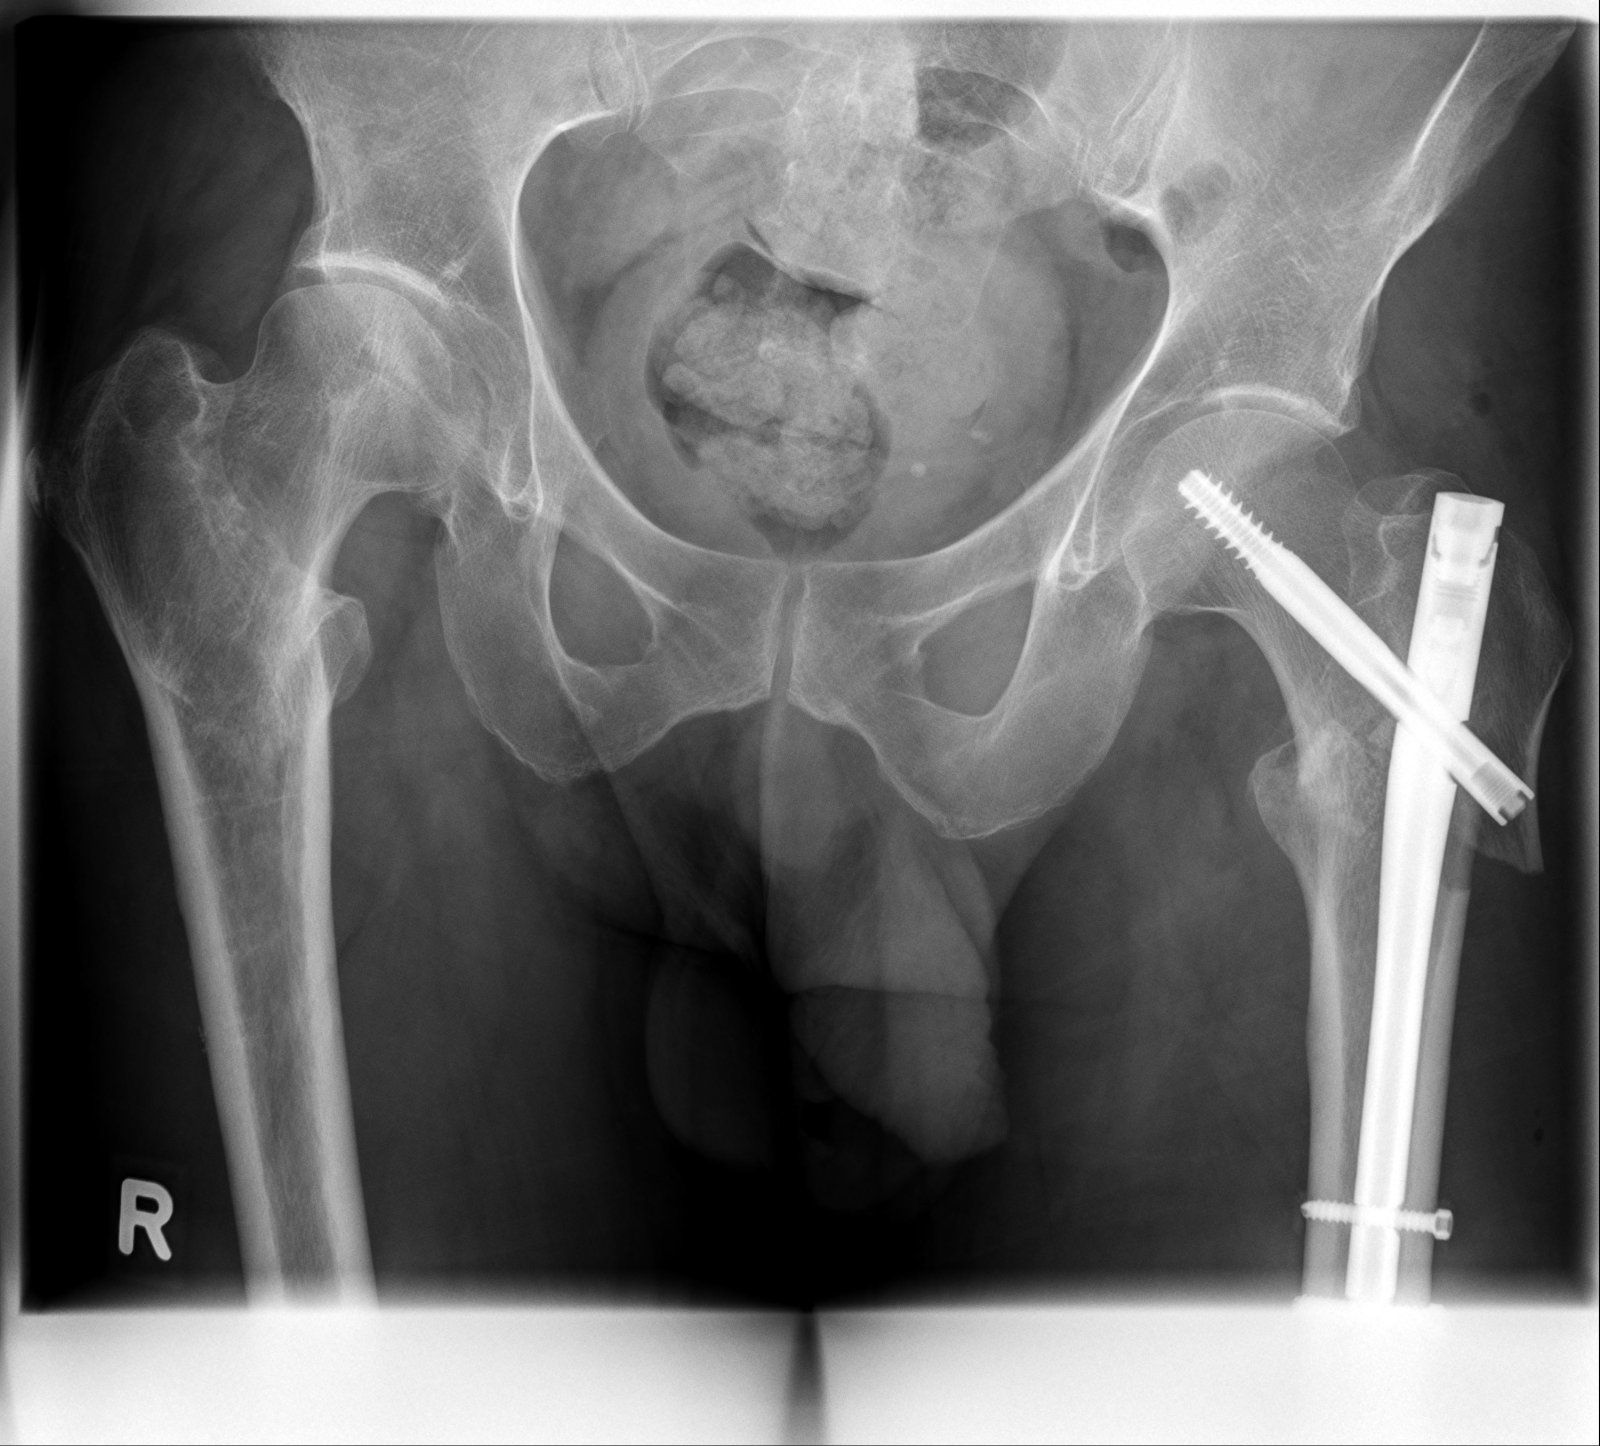

Titan ist es, darf im Körper bleiben.Puh, sieht ja heftig aus. Was verbauen die denn da so? Titan?

Zumindest mal der halbe Oberschenkel. Der Nagel ist 20cm lang, die Schraube oben 13cm. Ist schon massiv. Wie sagte ich vorhin zu meinen besten Freund: Nach meinen Tod lohnt sich das ausschlachten!Ach du meine Güte, hast du vor, langsam eine Maschine zu werden? Das halbe Bein besteht als Metall.

Zumindest mal der halbe Oberschenkel. Der Nagel ist 20cm lang, die Schraube oben 13cm. Ist schon massiv. Wie sagte ich vorhin zu meinen besten Freund: Nach meinen Tod lohnt sich das ausschlachten!